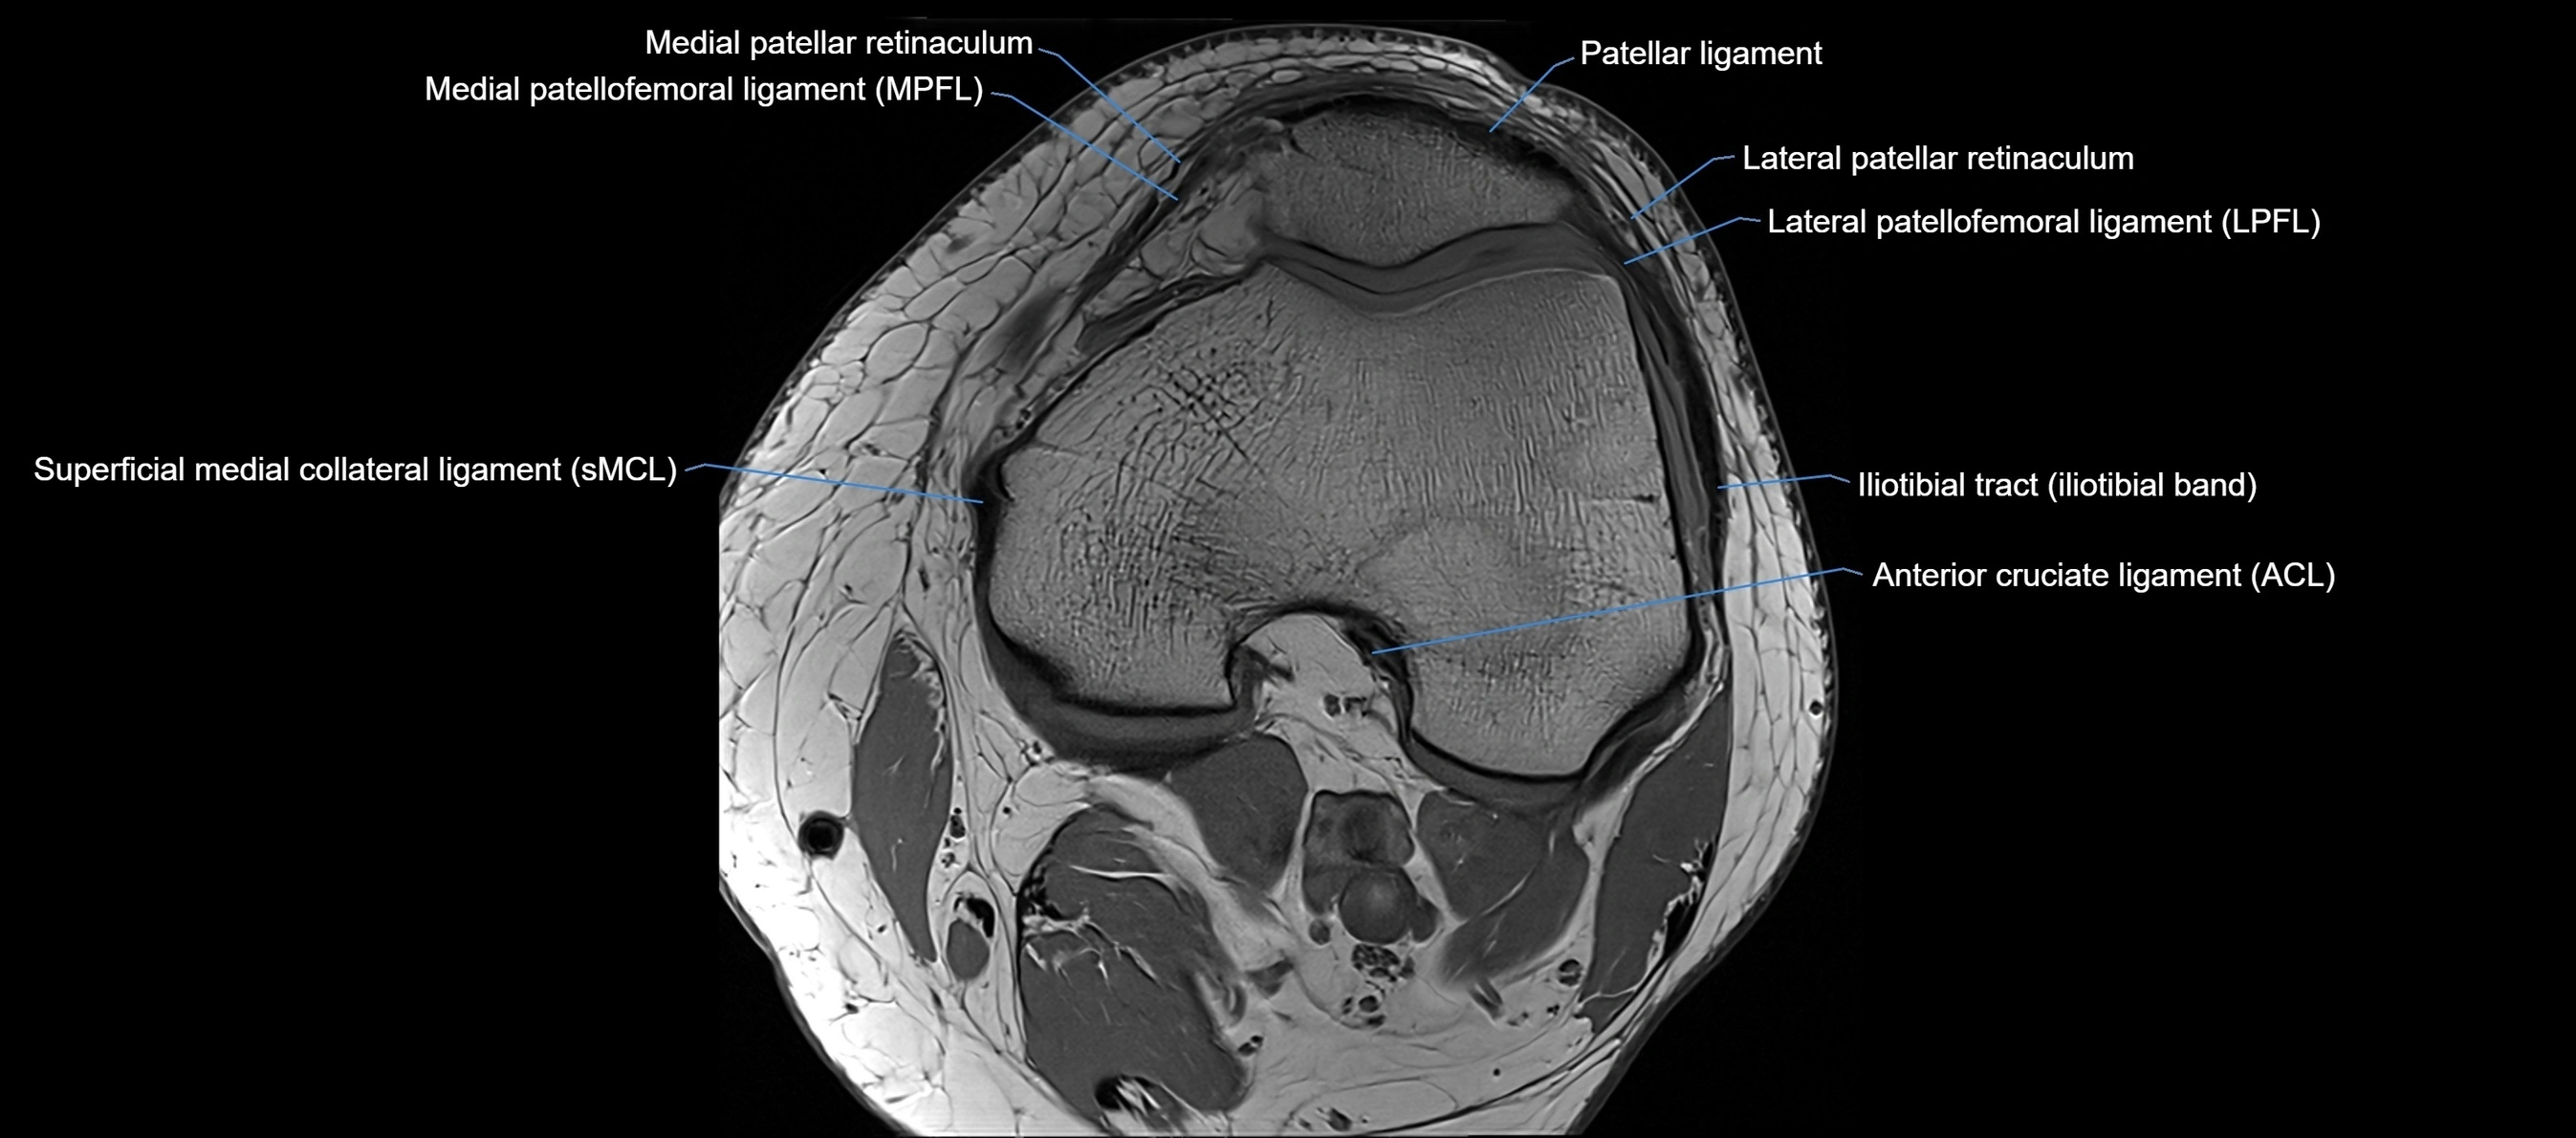

MRI Appearance

T1-weighted images:

• Normal ACL appears as a low-signal band-like structure crossing the intercondylar notch

• Surrounded by intermediate signal synovial fluid and fat planes

T2-weighted images:

• Normal ACL remains low signal

• Partial or complete tears appear as discontinuity, increased signal, or fiber laxity

STIR (Short Tau Inversion Recovery):

• Normal ACL shows dark low signal

• Acute injury shows bright hyperintensity due to edema and hemorrhage

Proton Density Fat-Saturated (PD FS):

• Normal ACL: dark, low-signal band

• Tears: bright intraligamentous hyperintensity, discontinuity, or abnormal course

MRI images

image